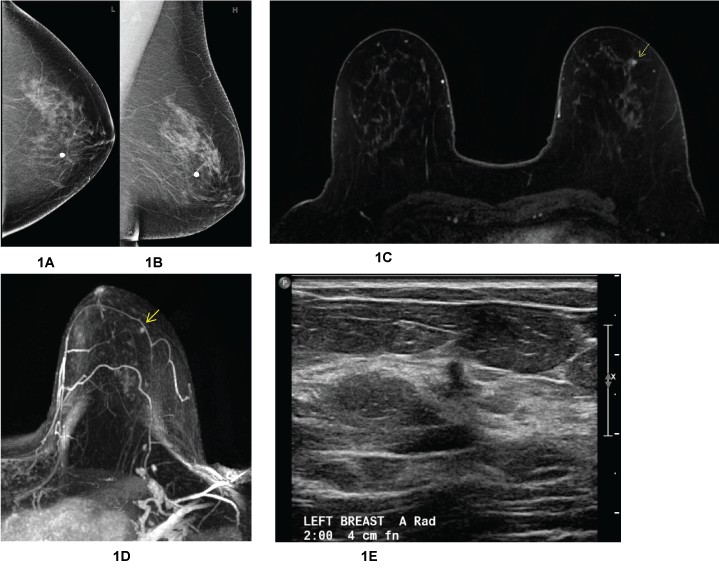

Addressing the cost and acquisition time limitations, active research in abbreviated protocol screening breast MRI shows promising results. In 2014, Kuhl and colleagues conducted a prospective observational reader study on an abbreviated breast MRI based on maximum intensity projection analysis of the early postcontrast T1 images (see example Figure 1D). Compared with the full protocol with an acquisition time of 17 minutes, the abbreviated protocol took 3 minutes to acquire with an average 28 seconds to read. Additionally, the abbreviated protocol showed equivalent diagnostic accuracy [30]. Since then, additional studies lend further evidence that the abbreviated screening protocols may replace the full protocols in the future without sacrificing diagnostic accuracy [31-33].

Figure 1: The CC (1A) and MLO (1B) mammogram of the left breast in a patient with personal history of breast cancer were read as normal. Subsequent breast MRI performed for history of breast cancer (1C, T1 post-contrast with fat subtraction and 1D, T1 post-contrast with fat subtraction and dynamic subtraction maximum intensity projection) showed a 6 mm mass in the left breast at the 2:00 position (yellow arrows) which was mammographically occult. Second look ultrasound (1E) showed a corresponding irregular hypoechoic mass. Subsequent ultrasound-guided biopsy yielded Invasive Ductal Carcinoma grade 2.